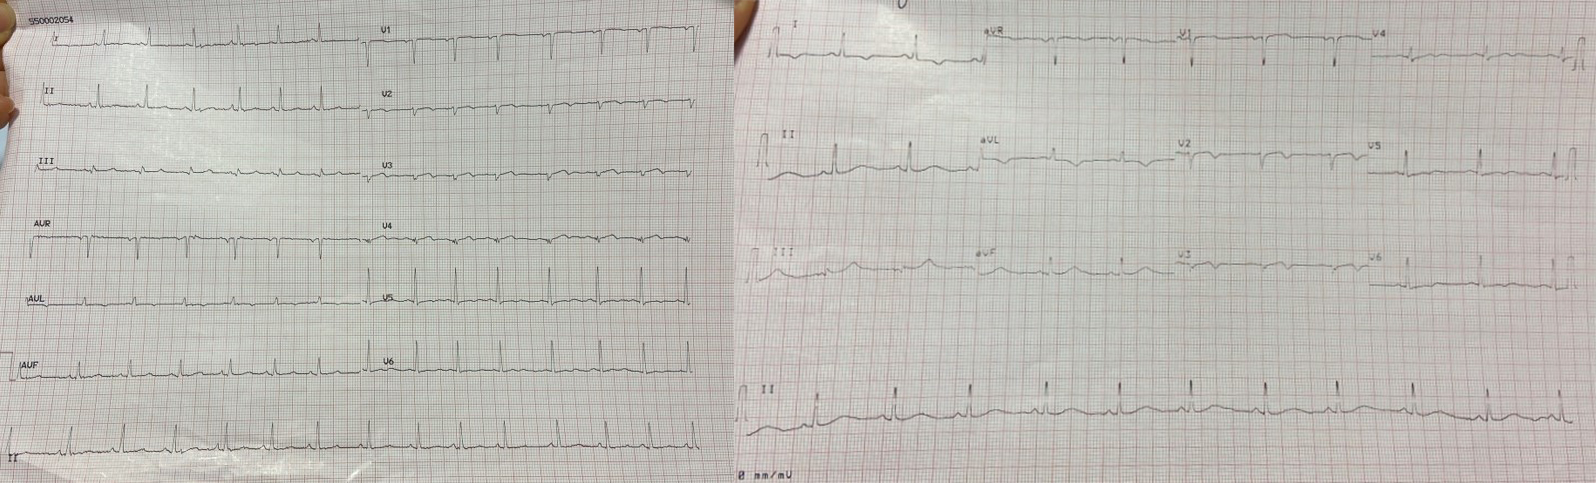

During the patient’s hospital stay, she experienced several episodes of acute chest pain. A re-evaluation of the ECG during these episodes revealed isodiphasic T waves in leads V2 and V3 (Fig. 7).

Fig. 7.

Fig. 7.A re-evaluation of the ECG during episodes of acute chest pain revealed isodiphasic T waves in leads V2 and V3. ECG, electrocardiogram.

When the ECG was recorded at rest, without symptoms, it displayed negative T waves in the extended-anterior region (Fig. 8).

Fig. 8.

Fig. 8.ECG at rest, in the absence of symptoms, displays negative T waves in the extended-anterior region. ECG, electrocardiogram.